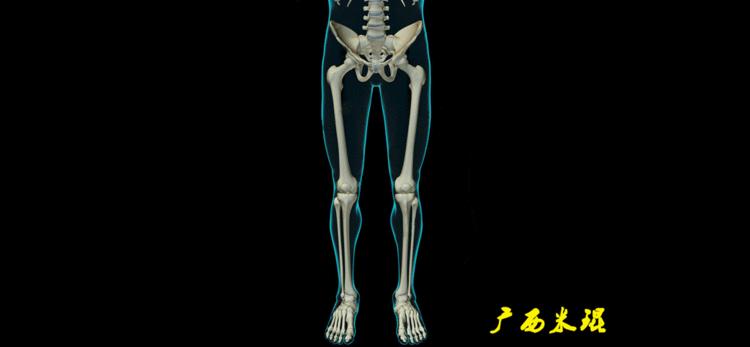

下肢力线及相关角度测量是骨科医生必须要掌握的基础知识,临床上关节疼痛的诊断、截骨矫形和关节置换手术前后等都需要用到这方面的知识,脑海中还没有这方面的概念就去给病人诊断甚至手术治疗,后果是可怕的。刚开始的时候可能感觉这些东西很难,其实只要掌握要点,反复实践,就很快能够熟练的使用它。

下肢力线及相关角度测量的前提是必须拍摄标准的站立位也就是负重位的下肢全长片。目前这样的照片都是放射科的技师在电脑上拼接出来的,大部分医院的DR都能够做到这一点。

无论如何,拍摄出来的下肢全长片必须包含髋关节中心、膝关节中心及踝关节中心,否则对临床是无用的。有了一张下肢的全长照片,我们需要确定下肢关节的中心点,通过中心点画出下肢的各种轴线,然后利用轴线与关节线的相交得出各种所需要的角度。